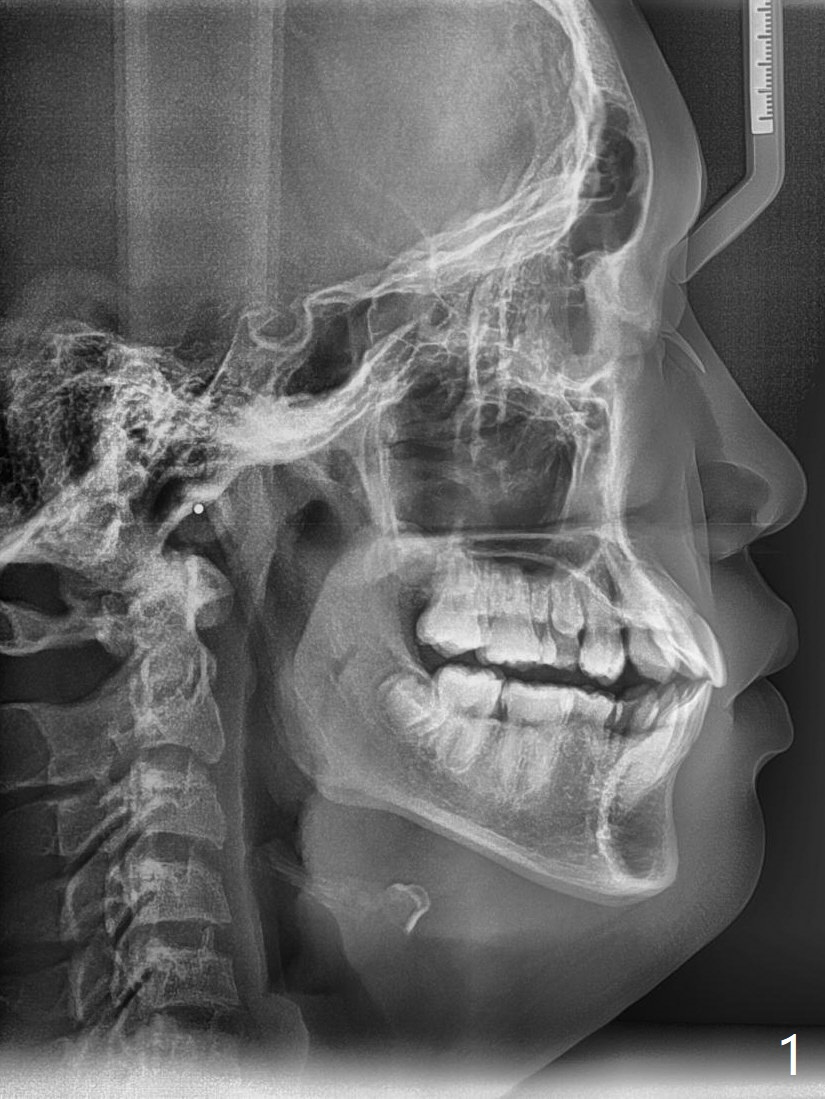

Pre-operative cephalometric X-ray shows convex facial profile (Fig.1). In fact tracing (a few days after banding) shows bimaxillary protrusion (SNA, SNB (88 and 87 degrees vs. 82, 80 (normal)). It appears that extraction orthodontics is indicated (UR4, UL5 (impacted) and LEs). The facial and upper dental midlines seem to coincide (Fig.2). No brackets or bands are placed at UR4 (because of non-cooperative (hyperactive)), LEs (Fig.3,4), or L7s (incomplete eruption, data not shown). Note wire bending between the canines and incisors, as related to correction of overbite. Shrinkable tubes are used in the region without bracket to prevent tissue injury. The upper arch seems to elongate (Fig.5, as compared to the lower one (Fig.6)). It appears that UR4 and UL5 should be extracted for normal profile and alignment. Cephalometric tracing shows that SNA and SNB are 79 and 85º, respectively, suggesting extraction (Fig.7).